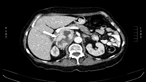

Limitations of CT scanning in Bosniak staging of renal cystic carcinoma

A S Wasim and F Mumtaz

Journal of Surgical Case Reports, Volume 2018, Issue 4, April 2018, rjy052, https://doi.org/10.1093/jscr/rjy052